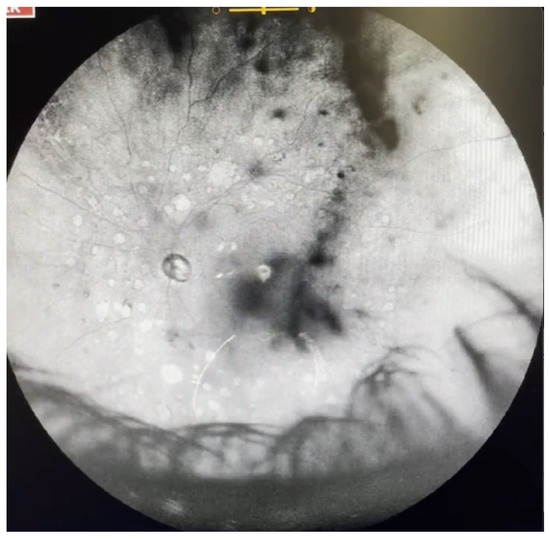

Figure 4.

Ultra-widefield IRcSLO image of an eye with Grade 2 vitreous floaters. Dense shadows are observed outside the macular area, in the superotemporal periphery, overlying an area of lattice degeneration. A Weiss ring is also visible outside the macular area (arrow). See also Video S4.